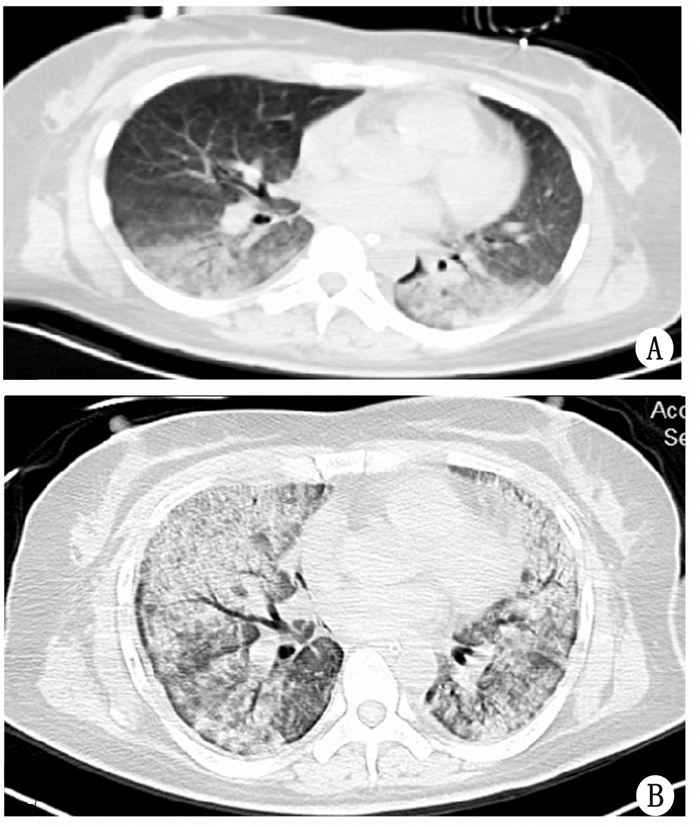

病例3患者,女,50岁,既往体健,长期工作于某金铅厂。因“吸入工业气体致胸闷、气短2 d,加重半小时余”于2016年3月3日入院。入院2 d前工作期间因吸入泄漏的工业气体(主要成分为二氧化硫)后致胸闷、气短,伴恶心,呕吐胃内容物500 mL,无发热及意识障碍,当地医院以“铅中毒”予以对症处理,效差,遂转我院,半小时前转运途中胸闷、气短加重。查体:体温36.0℃,心率116次/min,呼吸频率42次/min,血压132/80 mmHg,SpO2 66%(简易呼吸器辅助呼吸);神志昏睡,颜面部、双侧眼睑红肿;呼吸运动增强,叩诊浊音,双肺可闻及少量湿性啰音;余心脏、腹部、神经反射未见异常;诊断为:① 急性重症二氧化硫中毒重症肺炎ARDS;② 颜面部及眼部化学性损伤;查白细胞数17.7×109/L,中性粒细胞% 97.5%,降钙素原0.784 ng/mL,C反应蛋白60.7 mg/L;给予气管插管、呼吸机辅助呼吸(压控,FiO2 75%,PEEP 10 cmH2O,呼吸频率15次/min,PC 16 cmH2O)、哌拉西林他唑巴坦抗感染、小剂量糖皮质激素抑制炎症反应及对症处理,查PaO2 57 mmHg,PaCO2 43 mmHg,乳酸1.8 mmol/L,查胸部CT示:两肺间质性炎症(图 5 A)。患者低氧血症难以纠正,经肺复张可短时性改善,但氧合指数仍持续低于200 mmHg。11 d后复查胸部CT提示患者ARDS较前明显加重(图 5 B),予VV-ECMO治疗(转速2 200 mL/min,氧流量4 L/min), 氧分压明显升高(>100 mmHg)、感染指标改善、但监测胸片示肺部情况无明显好转,家属考虑经济原因等放弃继续治疗,于ECMO使用14 d后自动离院。

| A为入院时肺部CT提示间质渗出水肿,背侧为著;B提示肺部病变较前明显加重。 图 5 患者3入院CT |

本研究提供了参考意义,对于此类肺部病变可逆性强的患者救治具有重要参考价值。但病例3与前两例不同,该病例为有害气体通过呼吸道直接进入肺部而产生肺损伤。二氧化硫吸入后,在呼吸道黏膜表面与水结合生成亚硫酸,进而经氧化成硫酸,对呼吸道黏膜具有强烈的刺激作用。即可以引起反射性的支气管痉挛,也可直接灼伤呼吸道上皮细胞使细胞坏死、分泌增加。吸入大量高浓度二氧化硫后,引起肺部充血、水肿,甚至肺损伤的发生。有研究报告显示轻中度中毒经积极对症处理后短期即能缓解[18],但重度二氧化硫中毒即可引起反复加重的ARDS,又具有诱导产生自由基、引起肺组织纤维化等病理改变的慢性毒性作用[19],具有病情反复迁延、反复加重、恢复周期长、疗效差等特点。结合病例3中毒史及迅速出现的影像学异常改变,考虑重度的肺损伤,与上述特征相一致,尽管给予激素等积极处理,病情仍呈加重趋势(图 5),引起医疗费用增加等严重问题,使患者的预后进一步恶化。这与百草枯中毒,引起肺纤维化、呼吸衰竭的发展过程极其类似,但由于除早期阻断毒物吸收外,尚无明确有效的药物可供选择[20-21],ECMO作为一种对症支持治疗手段对疾病的进展并无逆转作用,理论上并不能改善患者的预后,少量报道显示ECMO可能为等待肺移植的百草枯中毒患者提供过渡作用,但仅部分患者最终获得成功[22-23]。因此对于此类可逆性较差的患者在应用ECMO时,需谨慎考虑利弊及长期存活、近期肺移植的可能性,应结合病情、社会因素等综合考虑。